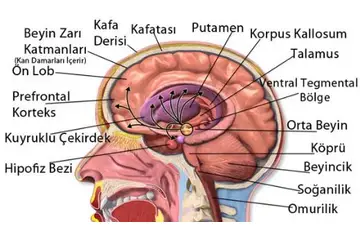

Bebeklerde beyin kistleri, genellikle doğumdan önce veya doğum sırasında oluşabilen sıvı dolu keseciklerdir. Bu kistler, beyin dokusunda veya çevresinde yer alabilir ve çoğu zaman zararsızdır. Ancak bazı durumlarda, beyin kistleri beyin fonksiyonlarını etkileyebilir ve tedavi gerektirebilir. Bu makalede, bebeklerde beyin kistlerinin belirtileri, tanısı ve tedavi yöntemleri hakkında detaylı bilgi verilecektir. Bebeklerde Beyinde Kist Belirtileri Bebeklerde beyin kistlerinin belirtileri genellikle kistin boyutuna, konumuna ve etkilerine bağlıdır. Belirtiler şunları içerebilir:

Bu belirtiler, kistin beyin üzerindeki etkilerine bağlı olarak değişiklik gösterebilir. Dolayısıyla, ebeveynlerin bebeklerinde bu tür belirtiler gözlemlemesi durumunda hızlı bir tıbbi yardım alması önemlidir. Bebeklerde Beyin Kistlerinin Tanısı Bebeklerde beyin kistlerinin tanısı genellikle aşağıdaki yöntemlerle yapılır:

Bu tanı süreçleri, doktorun kistin doğasını anlamasına ve uygun tedavi yöntemini belirlemesine yardımcı olur. Bebeklerde Beyin Kistlerinin Tedavisi Bebeklerde beyin kistlerinin tedavisi, kistin türüne, boyutuna ve bebeğin genel sağlık durumuna bağlı olarak değişiklik göstermektedir. Tedavi seçenekleri şunlardır: